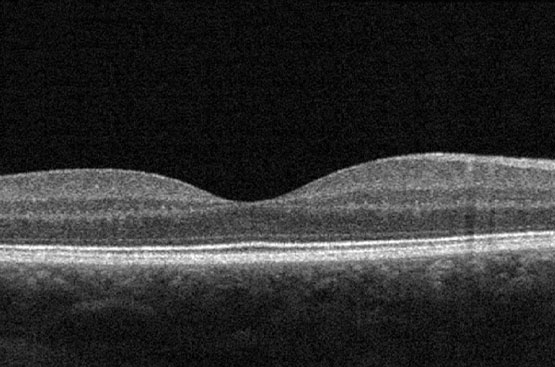

Tomografia A Coerenza Ottica (OCT)

Diagnosi e cura della maculopatia, dell'edema maculare diabetico e delle patologie della retina